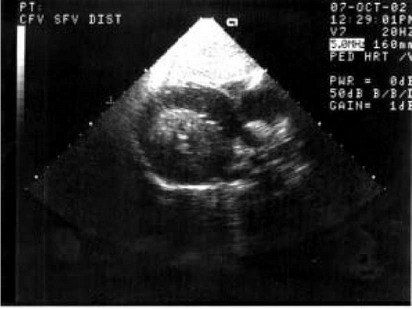

Рис. 85.

Фиброма межжелудочковой перегородки у девочки 12 лет. На эхокардиограмме опухоль неоднородной консистенции полно -стью прорастает межжелудочковую перегородку и имеет преимущественный рост в полость левого желудочка. мости из-за прорастания опухоли в проводящую ткань межжелудочковой перегородки.